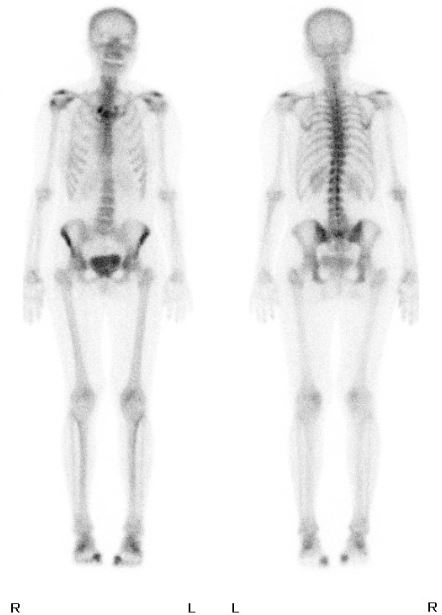

Knochen-Szintigraphie

Ein weiterer Schritt in der Diagnostik ist die Knochen-Szintigraphie, die Untersuchung des Skeletts auf Metastasen. Dabei wird eine schwach radioaktive Substanz injeziert, die dann in den Aufnahmen durch eine Gammakamera, Bereiche mit erhöhtem Umbau, wie Entzündungen, degenerative Veränderungen (Arthrose), Rheuma, Brüche oder Metastasen sichtbar macht.

Ganzkörperskelett-Szintigraphie

Ich sitze wieder im Wartezimmer und hoffe inständig auf gute Nachrichten. Eine halbe Stunde später werde ich zum Arzt gerufen. Mein komplettes Skelett, vorn und hinten auf dem Bildschirm. Er könne lediglich altersgemäße Abnutzungserscheinungen erkennen, besonders an den Schultern und den Füßen (wohl vom vielen Klettern!). Mein ganzes Skelett sei Metastasen-frei…

Ich fühle mich plötzlich leicht, so leicht. Draußen falle ich meiner Tochter in die Arme und schluchze vor Erleichterung. Nun steht fest: Ich habe KEINE Metastasen!!! (Außer, was ist mit meinen Lymphknoten!?)